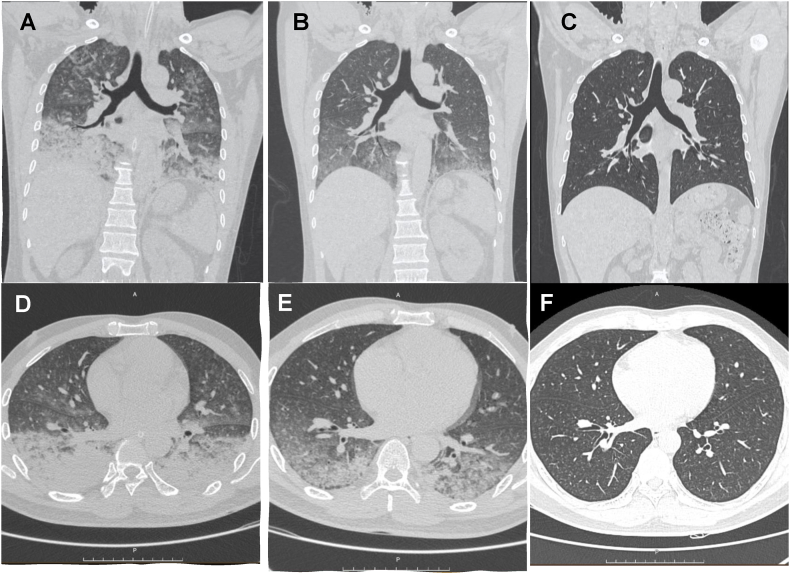

氯气吸入继发急性呼吸窘迫综合征(ARDS)是一种罕见但严重的疾病,如果不及时处理,可导致严重的呼吸衰竭。本病例报告提出一名43岁男性在泳池维修期间意外接触氯气后发展为ARDS。患者病情迅速恶化,症状进展为急性肺水肿和严重低氧血症,需要立即转至重症监护室(ICU)。最初的治疗包括无创通气,但患者很快需要气管插管和机械通气。尽管病情进展迅速,但患者对积极的ICU管理反应良好,包括氧气治疗、机械通气和药物支持。值得注意的是,患者在7天内完全康复,出院时病情稳定。与其他病因相比,本病例强调了氯气吸入引起的ARDS预后良好的可能性,强调了及时干预和ICU专科护理的重要性。

Acute respiratory distress syndrome (ARDS) secondary to chlorine gas inhalation is a rare yet critical condition that can lead to severe respiratory failure if not managed promptly. This case report presents a 43-year-old male who developed ARDS after accidental exposure to chlorine gas during pool maintenance. The patient's condition deteriorated rapidly, with symptoms progressing to acute pulmonary edema and severe hypoxemia, requiring immediate transfer to the intensive care unit (ICU). Initial treatment included non-invasive ventilation, but the patient soon required tracheal intubation and mechanical ventilation. Despite the rapid disease progression, the patient responded well to aggressive ICU management, including oxygen therapy, mechanical ventilation, and pharmacological support. Remarkably, within seven days, the patient fully recovered and was discharged in stable condition. This case highlights the potential for a good prognosis in ARDS due to chlorine gas inhalation compared to other etiologies, emphasizing the importance of timely intervention and specialized care in the ICU.